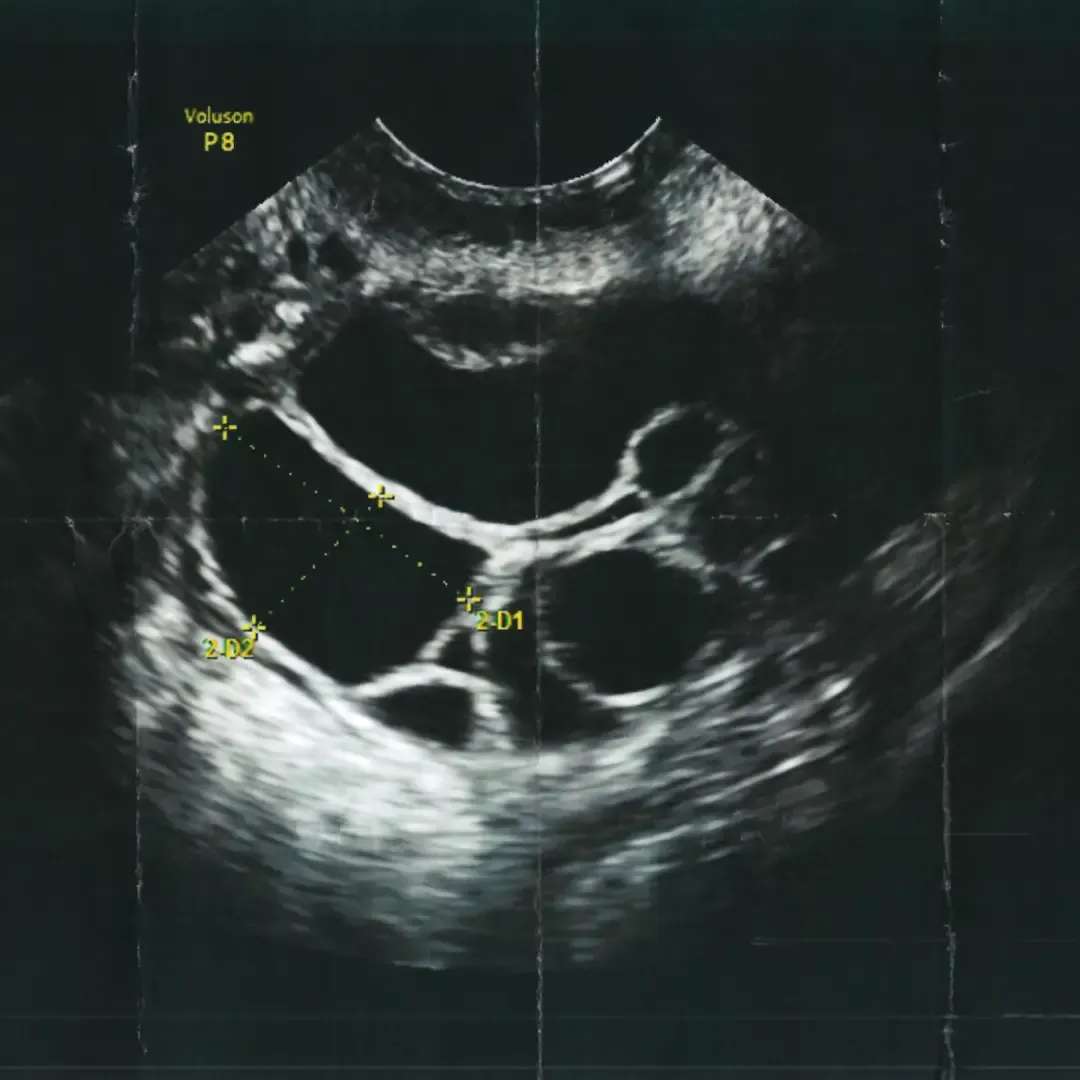

Professor Fleming’s team demonstrated how ultrasound scan can be used to identify and measure follicular growth.

The TFP Fertility journey began when Professor Fleming’s team demonstrated how ultrasound scan can be used to identify and measure follicular growth of eggs.

This was pivotal for the fertility sector, enabling doctors to replace invasive keyhole surgery for egg retrieval with a simple needle directly into a follicle, directed with ultrasound. This minimised risks to patients and removed surgery recovery.

Through the evolution of technology, ultrasound has become more sophisticated and precise. We now use ultrasound to:

Predict how a person may respond to treatment by counting the follicles in their ovaries

Identify underlying issues that may prevent an embryo from implanting

Perform embryo transfers with greater precision, ensuring the embryo is transferred safely and quickly

The TFP Fertility journey began when Professor Fleming’s team demonstrated how ultrasound scan can be used to identify and measure follicular growth.

This was pivotal for the fertility sector, enabling doctors to assess follicular development during an IVF cycle. Treatment became far less invasive for the patient, particularly during egg collection, allowing doctors to direct the needle into the follicle to retrieve the egg rather than performing a laparoscopy under general anaesthetic, minimising the risk to the patient.

Through the evolution of technology, ultrasound has become more sophisticated and precise, providing better images and resolution. Because of this, ultrasound can now be used to: